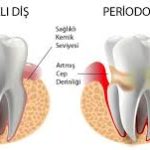

Periodontitis, diş eti ve diş çevresindeki dokuların kronik enfeksiyonu ile karakterizedir. Bu enfeksiyonlar sistemik inflamatuar yanıtı tetikleyebilir:

- Periodontal patojenler (ör. Porphyromonas gingivalis, Aggregatibacter actinomycetemcomitans) lokal inflamasyon yaratır.

- Artan sistemik inflamasyon, ateroskleroz gelişimini hızlandırabilir, damar içi plak oluşumuna katkıda bulunur ve mevcut damar lezyonlarını destabilize edebilir.

- Günlük diş fırçalama, diş eti kanamaları veya periodontal cep derinliği ile bakteriler kana geçebilir.

3. Endotelyal disfonksiyon

- Periodontal enfeksiyonlar, endotelyal hücrelerde fonksiyon bozukluğu (endotelyal disfonksiyon) yaratabilir.